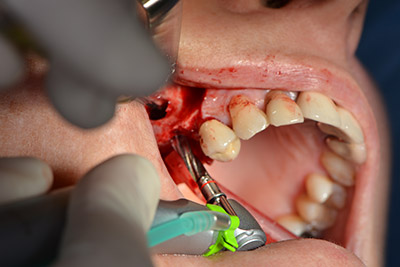

The following holes were drilled at a reduced speed of 300 rpm. The Implantmed demonstrated its true capability at this stage. The surgical protocol can be preset – the various positions can be selected simply by pressing the “P” position of the foot control (Fig. 10 to 11).

The next programmed position is the placement of the implant and in our practice it is preset to a force of 32 Ncm (Fig. 12).

The next step was the sinus floor elevation with simultaneous implantation. The Implantmed also had a presetting at the first position for the buccal fenestration of the maxillary sinus wall.

The fenestration was prepared at 35,000 rpm and then the nasal mucosa were prepared in the cranial direction (Fig. 13 to 14).